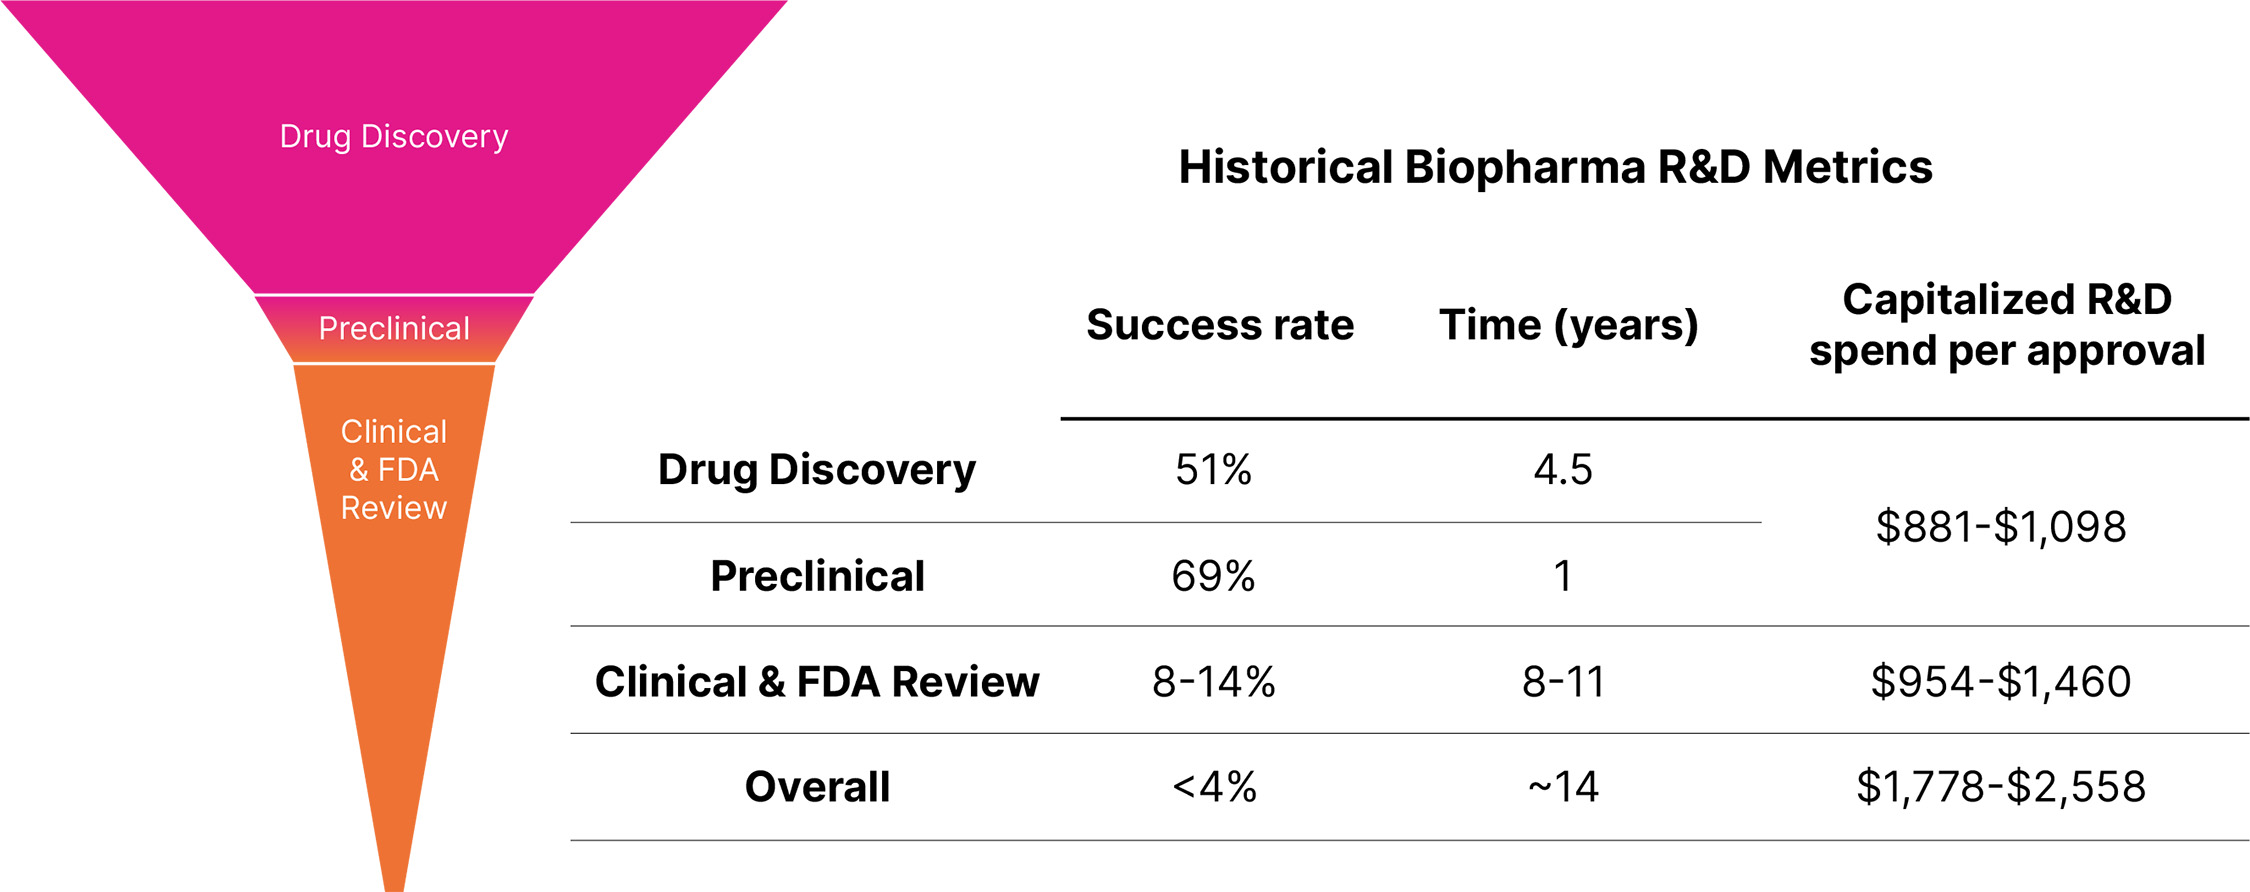

Figure 5. Historical biopharma industry R&D metrics. The primary driver of the cost to discover and develop a new medicine is clinical failure. Less than 4% of drug discovery programs that are initiated result in an approved therapeutic, resulting in a risk-adjusted cost of approximately $1.8 to $2.6 billion per new drug launched.3,4,5,6,7